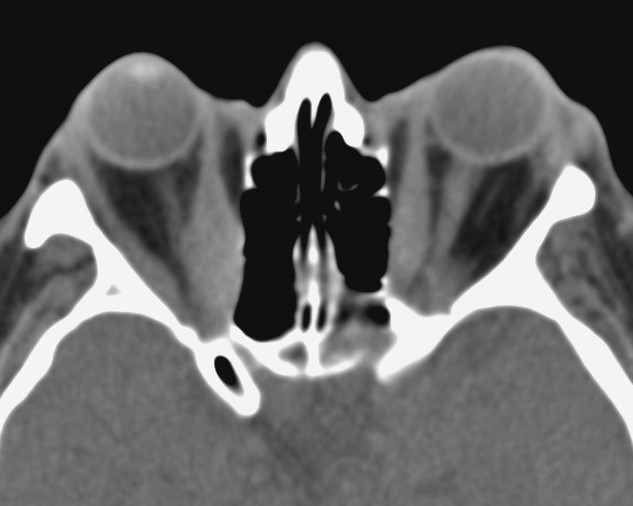

Right Proptosis

Bilateral thyroid eye disease (proptosis, exophthalmos)

Investigations Which Neuroimaging Test is Best to Evaluate the Etiology of Proptosis?

- CT scans are superior in most cases.

- MRI may be desirable in certain cases when optic nerve dysfunction is present.

- MRI is sensitive in identifying extraocular muscle oedema and other soft tissue.